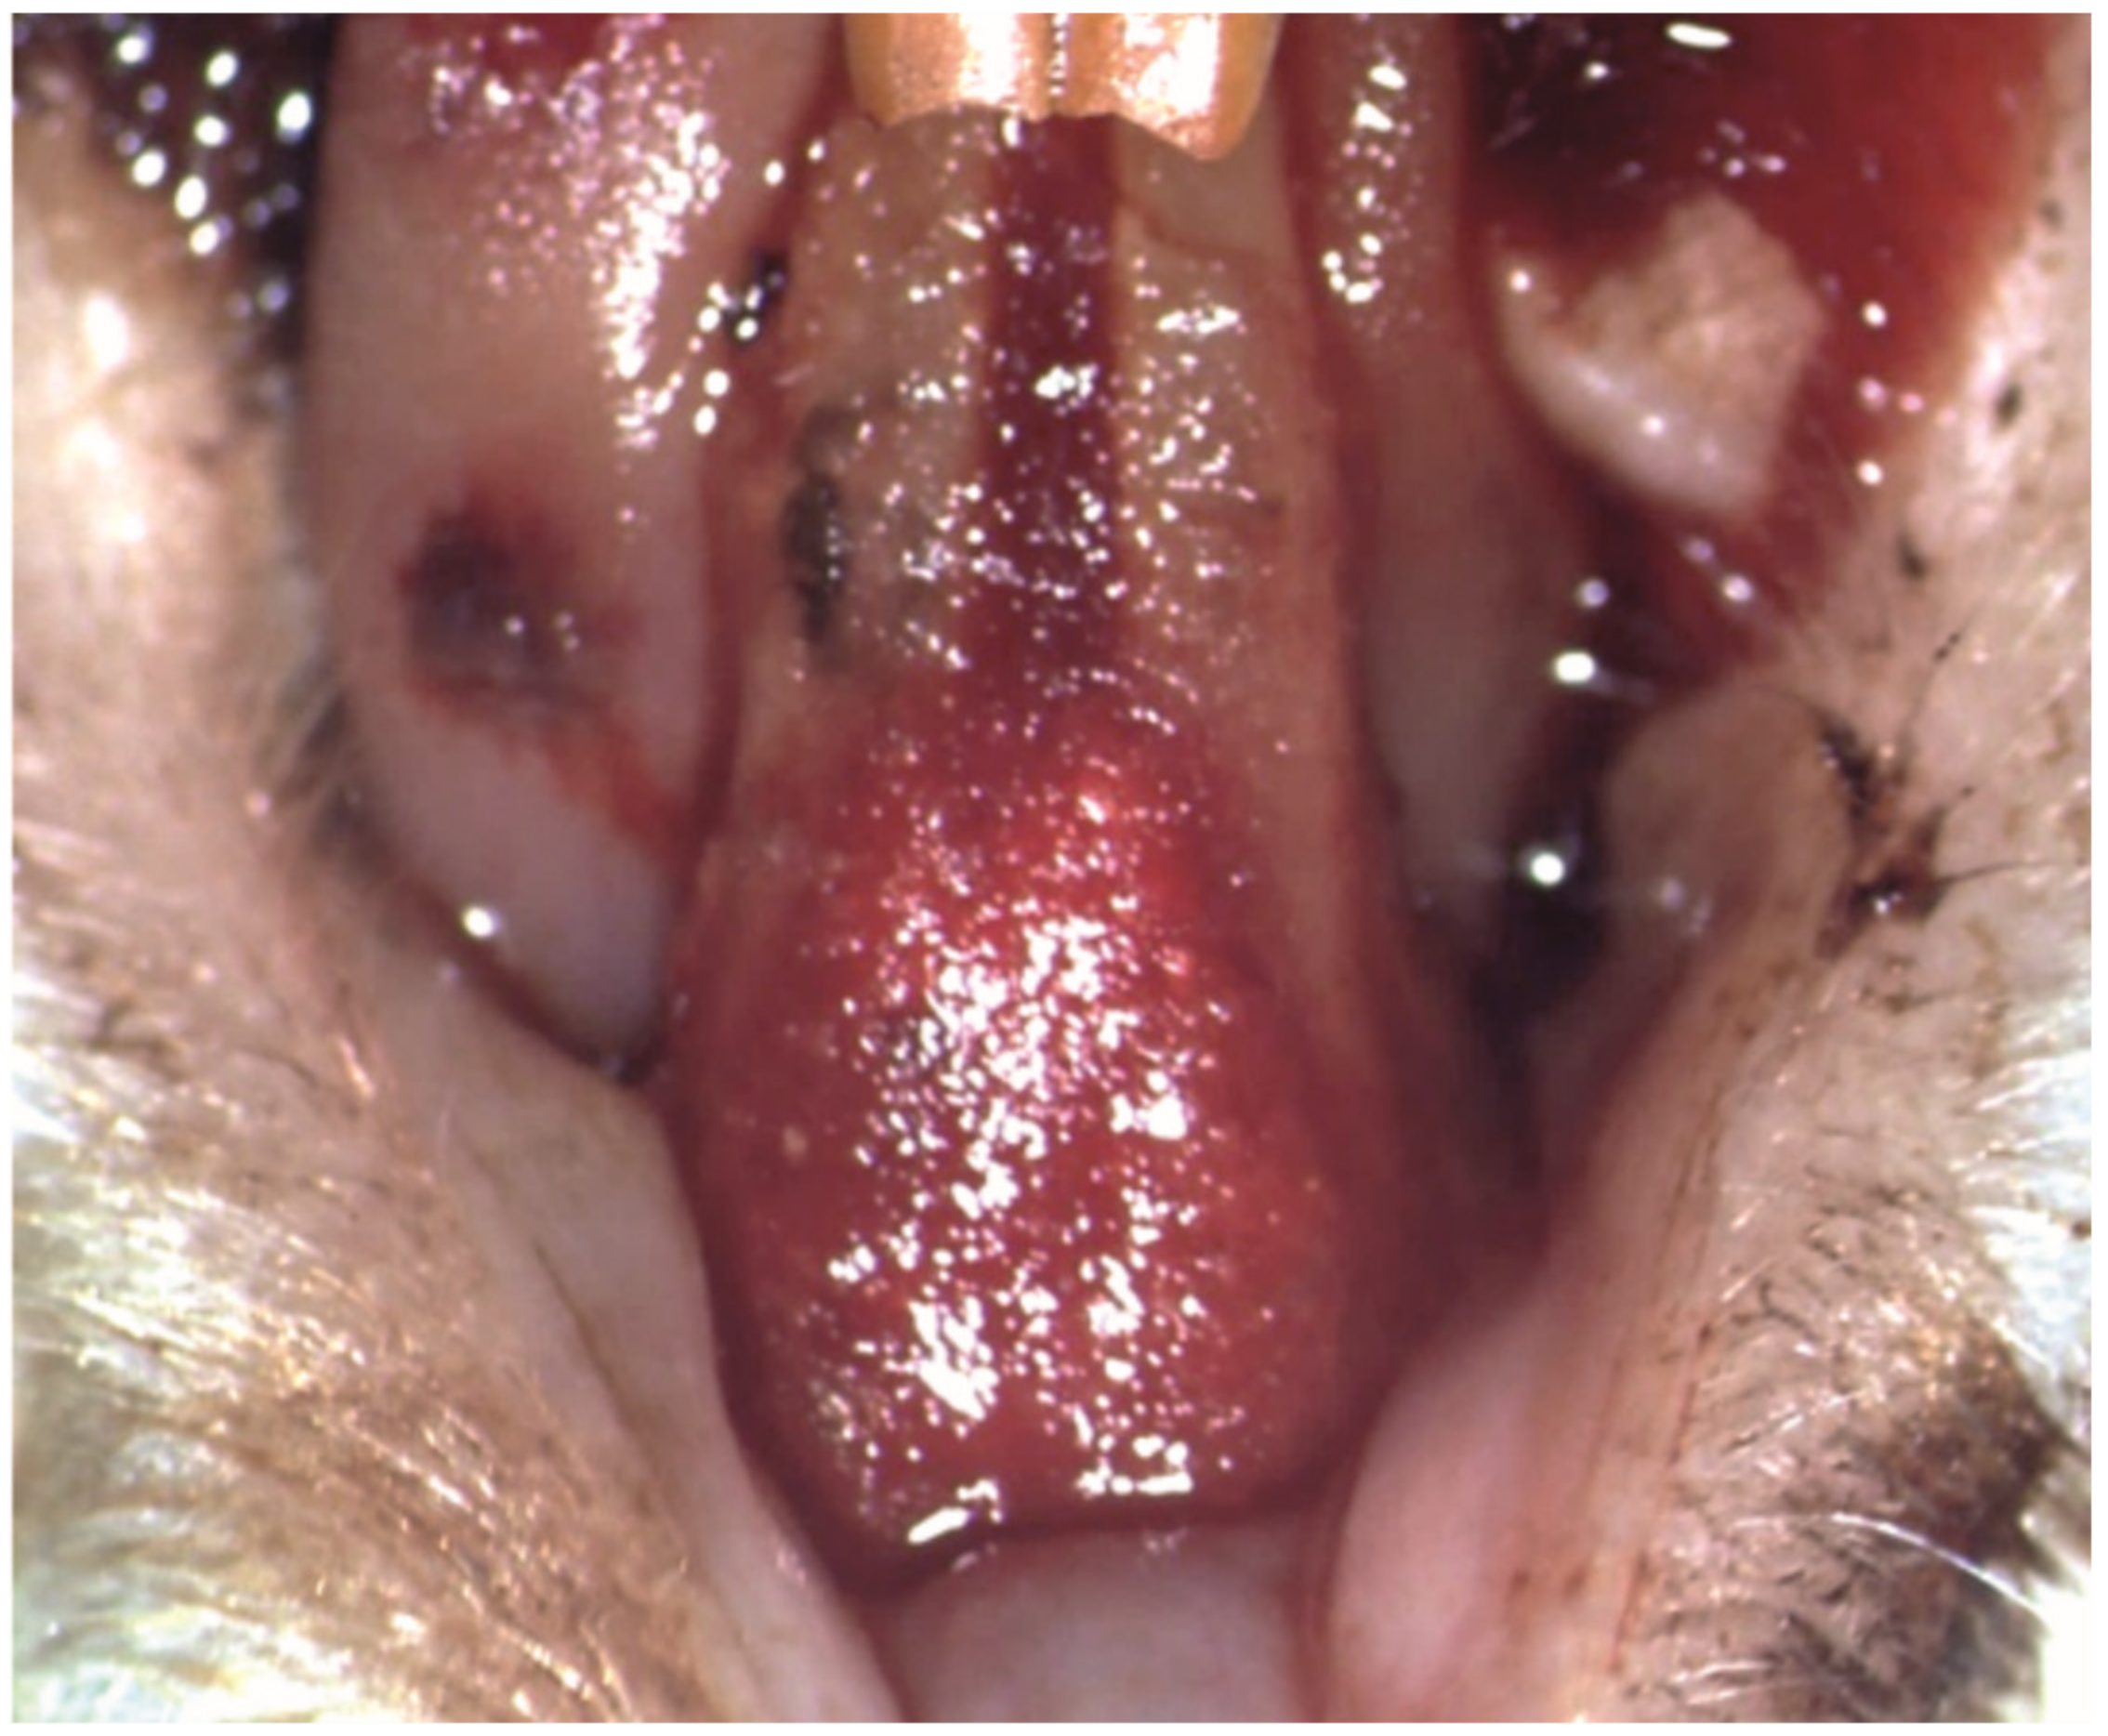

The periodontal pocket loaded with the new biomaterial was covered with a mucoadhesive buccal film, which became malleable and adhered to the periodontal tissues after hydration with sterile saline solution and the subsequent contact with saliva (Figure 5).

Figure 5.

Clinical aspect after the application of the mucoadhesive buccal film covering the periodontal pocket loaded with the electrospun nanofibers.